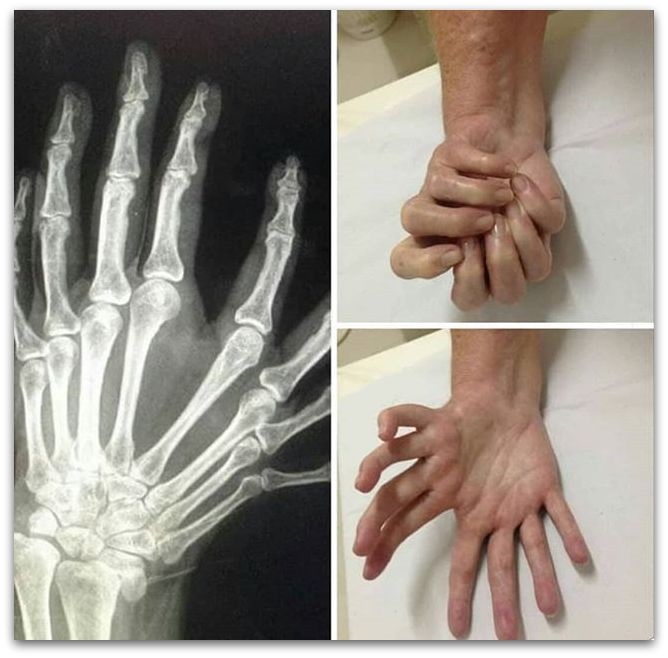

Синдром на туѓата рака

Потенцијалните опасни ситуации кои страдаат од овој хендикеп, не можат да го контролираат екстремитетите и тие дејствуваат непроизволно, но намерно. Тоа може да бидат доста опасни активности кои човек не може да контролира на било кој начин.

Специјалистите разјасни дека болеста може да биде предизвикано од оштетување на одредени делови од мозокот, Алцхајмерова болест или од тумор во главата.